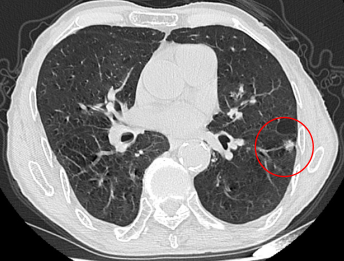

患者吴爷爷,90岁,胸部增强CT提示左肺高危肺结节,肺癌可能性极大。因患者高龄、肺功能较差,不能耐受外科手术,患者及家属对肺部高危结节非常担心。

左肺结节